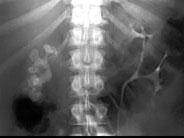

问题 女,39岁,腹痛,腹部平片+IVP如图所示,下列说法正确的是 ( )

选项 A、右肾集合系统内高密度影考虑为右肾结石 B、右肾集合系统内高密度影考虑为右肾结核钙化 C、右输尿管未见造影剂 D、左肾可见重复的肾收集系统 E、右肾集合系统内可见大的鹿角状高密度影

答案 ACDE